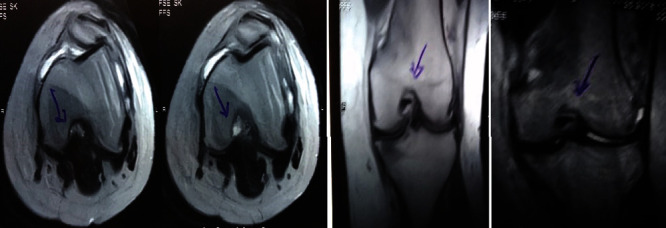

治療后一個月進行隨訪。在第一次細胞治療后,患者的疼痛明顯減輕。第二次療程后,她沒有疼痛,并注意到運動范圍有所改善。持續的物理治療也觀察到下肢肌肉力量的增加。從治療開始(11個月前)到最后一次隨訪(4個月前),患者按照建議的飲食和基于運動的方案減重了11公斤。因此,她現在整體身體健康,能夠更舒適地進行日常生活活動。表3顯示治療前后的MRI檢查結果。人物的圖1和的和圖2顯示半月板撕裂的治療前和治療后(1年后)圖片。觀察到損傷程度的改善圖2。